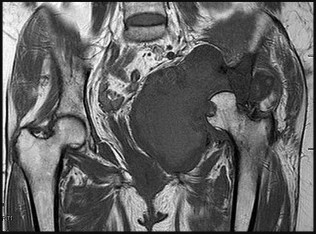

A 12-year-old obese male presents with left groin pain and an altered gait. Based on the presumed diagnosis of slipped capital femoral epiphysis (SCFE) shown in the representative radiograph, which of the following is the primary blood supply to the femoral head that is at highest risk for iatrogenic injury during percutaneous in situ pinning if the pin is placed in the posterosuperior quadrant?

The primary blood supply to the capital femoral epiphysis in children over the age of 3 is the posterosuperior retinacular vessels (lateral epiphyseal artery), which are terminal branches of the medial circumflex femoral artery (MCFA). During in situ pinning for SCFE, placement of the pin in the posterosuperior quadrant of the femoral neck/head places these extracapsular vessels at extreme risk of injury, potentially leading to avascular necrosis (AVN). Pins should ideally be placed in the center-center position to minimize this risk.